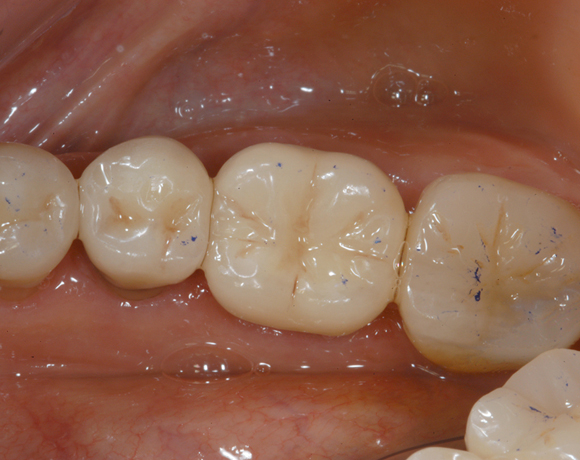

Empress II Presskeramik mit Eris Verblendkeramik bei einer Neuversorgung im Oberkiefer komplett und im Unterkiefer Vollkronen auf den Seitenzähnen.

Hier wurden der ganze Oberkiefer und die Seitenzähne im Unterkiefer mit neuen Kronen aus Empress 2 und mit Eris Verblendkeramik versorgt.